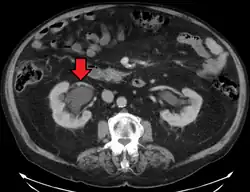

CT scan of bilateral hydronephrosis due to a bladder cancer -

Massive hydronephrosis as marked by the arrow -